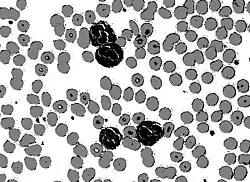

Circular thresholding is an algorithm for automatic image threshold selection in image processing. Most threshold selection algorithms assume that the values (e.g. intensities) lie on a linear scale. However, some quantities such as hue and orientation are a circular quantity, and therefore require circular thresholding algorithms. The example shows that the standard linear version of Otsu's method when applied to the hue channel of an image of blood cells fails to correctly segment the large white blood cells (leukocytes). In contrast the white blood cells are correctly segmented by the circular version of Otsu's method.